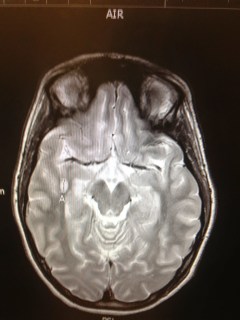

Our conversation came in response to our visit with her neurosurgeon. In describing her brain tumor he said, “It is small, like a jelly bean.” Later we asked her what color she would choose – thus the shocking disclosure that she would choose sour apple over watermelon. (In all fairness, I do really like those apple suckers that have caramel on the outside.)

| “A” marks the spot. It is on the right side – looking from the feet up |

It is really the Li Fraumeni Syndrome that has everyone concerned and we all agree that it needs to come out. It isn’t such a rush and will probably be scheduled in June or later. Scheduling is a bit tricky because they need a particular surgical suite with room for lots of equipment and computers. It sounds like the computer will do a lot of the work – our doctor is the chief pediatric neurosurgeon and has done well over 4,000 surgeries and over 1,500 of them are craniotomies. He was confident, likable and seemed to have good judgement – we feel that we are in good hands.

How am I feeling about this new little jelly bean in our lives? Since we have known about it for some time – today I am feeling relieved. Scheduling surgery a couple months out feels like I have some space to breathe. The risk of complications is low at this point. Recovery will probably include one night in ICU and the possibility of coming home the next day, with a very short time until Natalie is back to normal. Everything felt like good news today.